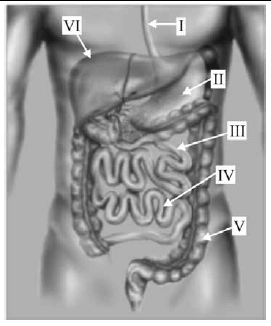

Com base na figura acima, que representa o trato digestório humano, julgue os itens de 71 a 77.

Em casos de insuficiência pancreática, a lipase gástrica é eficiente na prevenção à esteatorreia, pois possibilita que a absorção de triglicerídios de cadeia longa ocorra na estrutura indicada por IV.

Com base na figura acima, que representa o trato digestório humano, julgue os itens de 71 a 77.

Os ácidos graxos de cadeia curta produzidos na estrutura indicada por V tanto aumentam a absorção de eletrólitos e água quanto reduzem a carga osmótica de açúcares mal digeridos.

Com base na figura acima, que representa o trato digestório humano, julgue os itens de 71 a 77.

No processo denominado circulação entero-hepática, cerca de 5% dos sais biliares excretados pela estrutura indicada por VI são reabsorvidos como ácidos biliares no sítio indicado por IV.

Com base na figura acima, que representa o trato digestório humano, julgue os itens de 71 a 77.

A absorção de zinco, que ocorre, preferencialmente, na estrutura indicada por III, é prejudicada pela presença de oxalatos e de fitatos e pelo excesso de elementos como o magnésio, o cálcio e o ferro.

Com base na figura acima, que representa o trato digestório humano, julgue os itens de 71 a 77.

Os carboidratos passam pelo estômago mais rapidamente que as proteínas e as gorduras, e o principal local de sua absorção localiza-se na estrutura indicada por III.

Com base na figura acima, que representa o trato digestório humano, julgue os itens de 71 a 77.

O pepsinogênio, secretado pelas glândulas localizadas na estrutura indicada por II, é uma protease ativa, responsável pela modificação da forma e do conteúdo das proteínas.

Com base na figura acima, que representa o trato digestório humano, julgue os itens de 71 a 77.

Na estrutura indicada por I, o alimento é movido pela peristalse e o processo de deglutição é involuntário.